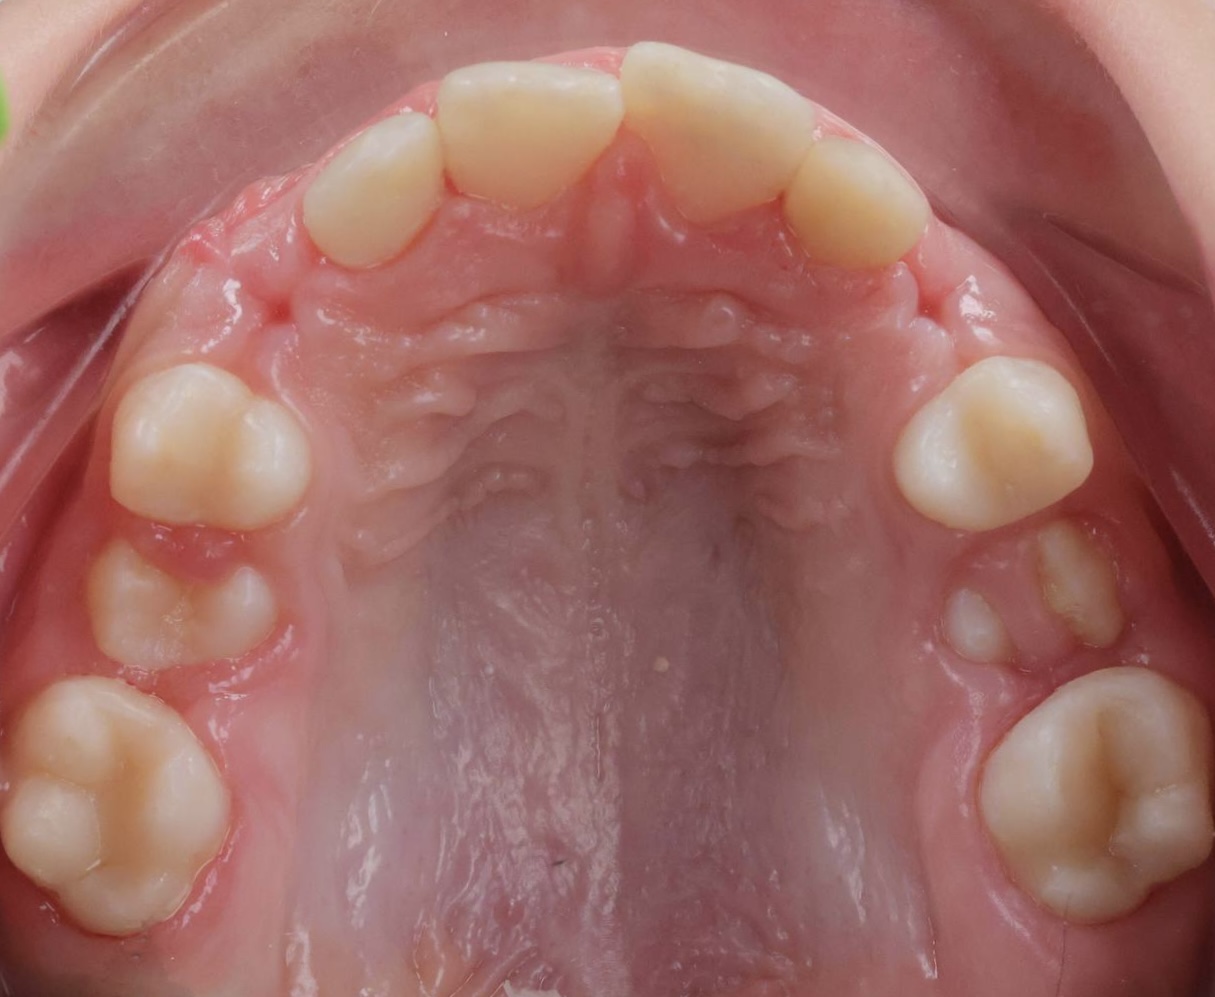

Дитина звернулася до нашої клініки разом із батьками зі скаргами на неправильний прикус. Під час первинного огляду було встановлено, що для досягнення правильного змикання зубів необхідно розпочати лікування з підготовчого етапу.

На представленому фото — результат після першого етапу лікування, на якому вже помітні позитивні зміни прикусу.

Як проходив перший етап лікування

На першому етапі було виконано розширення верхньої щелепи. Для цього дитині встановили незнімний розширювальний апарат на верхню щелепу, який дозволяє:

• створити достатній простір для правильного розташування зубів;

• покращити співвідношення щелеп;

• підготувати зубощелепну систему до наступних етапів ортодонтичного лікування.

Вже після завершення цього етапу прикус почав змінюватися, що є важливим показником ефективності лікування.

Поточний стан і подальший план

На даний момент дитина носить лицьову маску, яка допомагає скоригувати ріст щелеп і закріпити отриманий результат. Після завершення цього етапу планується подальше лікування з використанням брекет-системи для точного вирівнювання зубів і стабілізації прикусу.

Ортодонтичне лікування у дітей часто проходить поетапно, і саме ранній початок дозволяє досягти більш прогнозованого та стабільного результату в майбутньому.